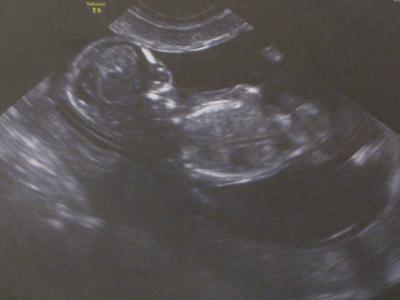

Guten Morgen, ich hatte ja versprochen, über unseren Ultraschall von gestern Abend zu berichten. Erst einmal ist mein Mann mit halbstündiger Verspätung eingetroffen, er war doch wirklich zu unserer alten Klinik gefahren (wir haben vor kurzem den Arzt gewechselt und wohl noch in Gedanken bei der Arbeit hat er automatisch den Weg zur alten Klinik gewählt, lol), aber die Sprechstundenhilfe war sehr nett und ich konnte warten bis er da war. Dann durfte erst einmal eine Studentin an mir Ultraschall üben (wir sind in einem Teaching Hosptital, also einem Krankenhaus, an dem Studenten ausgebildet werden, was für mich aber ok ist). Danach kam die Spezialistin, die auch gleich ein bisschen mit mehr Druck zur Sache ging. Das Positive: Der Zwerg ist in den letzten 4 Wochen über 4 cm auf 6.3cm gewachsen (ich war gestern bei 12+0), was wohl eher 12+2/12+3 entspricht. Da bei uns aber der Eisprung per Spritze ausgelöst wurde, weiß ich wann dieser war und bleibe somit auch beim 10.10. als ET. Herzschlag und alle anderen Werte auch super. Zwerg hat sich auch fleißig bewegt und mit Händchen und Beinchen gerudert. Hier in Spanien wird die Nackenfalte auch routinemäßig mitgemessen, wusste ich gar nicht, aber der Wert war mit 1,6mm in Ordnung. Allerdings war eine kleine Sache doch etwas besorgniserregend. Unser Baby hat Bluthochdruck, was in der Blutdruckkurve die erstellt wurde sichtbar wurde. Ich hatte das vorher noch nie gehört, lediglich Bluthochdruck bei Schwangeren, meiner war aber in Ordnung. Auch im Internet habe ich dazu nichts gefunden. Hat da von Euch schon jemand Erfahrung mit? Auf jeden Fall müssen wir nun in 4 Wochen nochmal einen Spezial-Ultraschall machen lassen, eigentlich wäre das hier erst in der 20 SSW wieder an der Reihe. Aber gut. Hoffen wir einfach, dass sich bis dahin alles normalisiert hat. Wir sind trotzdem glücklich, dass alles andere so gut aussieht und freuen uns schon auf Ostern, wenn wir meiner Familie die Neuigkeiten verkünden. Heute ist erstmal mein Boss dran. In 2 Stunden habe ich Meeting mit ihm. Anbei noch ein kleines Bildchen von gestern. Durch die Bewegungen des Zwergs nicht ganz so scharf wie die letzten Male ;) Allen noch einen wunderschönen Tag Sabrina

Bild zu US-Termin mit einem lachenden und einem weinenden Auge - Forum für Oktober - Mamis